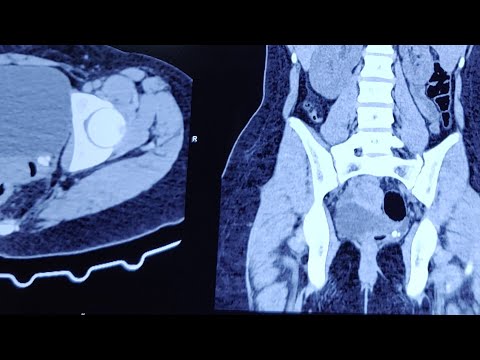

5.22.2020 Urology COViD Didactics - Pediatric Uroradiology: Case Based Learning

Calcification post endoscopic treatment for VUR masquerading sd VUJ calculus @Pediatric-Urologist

STING procedure; endoscopic treatment VUR in lower moiety duplication @Pediatric-Urologist

ASVNU Journal Club 8/14/2020- Management of Ectopic Ureters